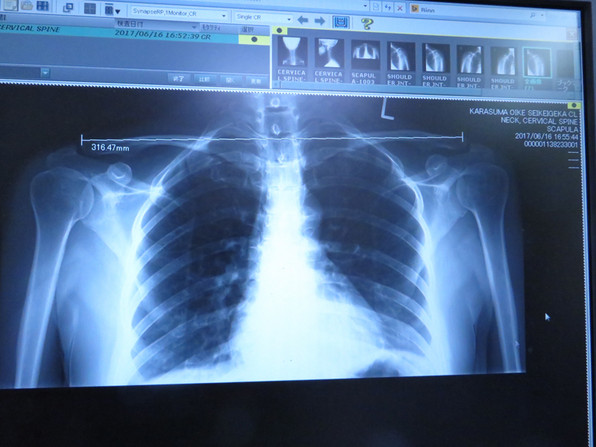

■ 肩が痛すぎるのです。しばらく治療に通うことにしました。

レントゲン写真は烏丸御池整形外科クリニックで撮っていただいたものです。

そもそも身体がゆがんでいると( ̄○ ̄;)( ̄○ ̄;)